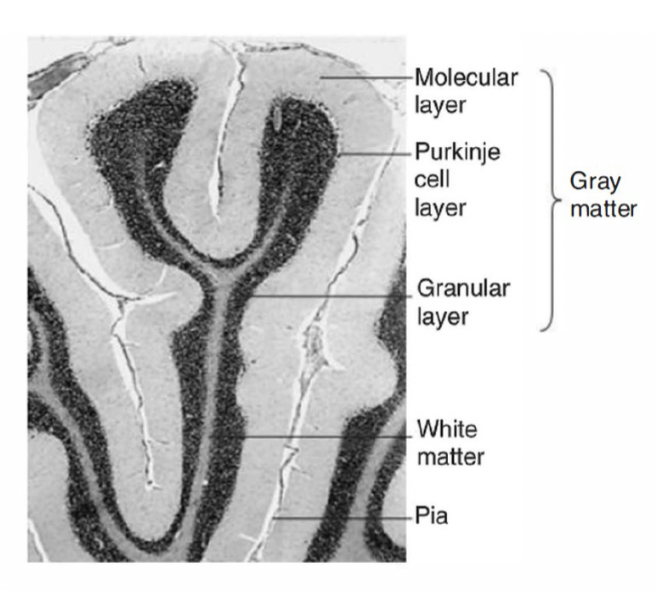

Layers of differentiated neurons in the grey matter

The cerebellar cortex consists of three layers of differentiated neurons (Granule, Golgi, Purkinje, Basket and Stellate):

Molecular: Contains cell extensions and some interneurons (basket cells and stellate cells)

Purkinje: Contains Purkinje neurons, whose axons project to the deep nuclei and are the only exit route from the cortex

Granular: The most abundant layer in terms of cells. Among them are the granules cells, whose ascending axons branch out in a "T" shape, forming parallel fibres that synapse on the Purkinje